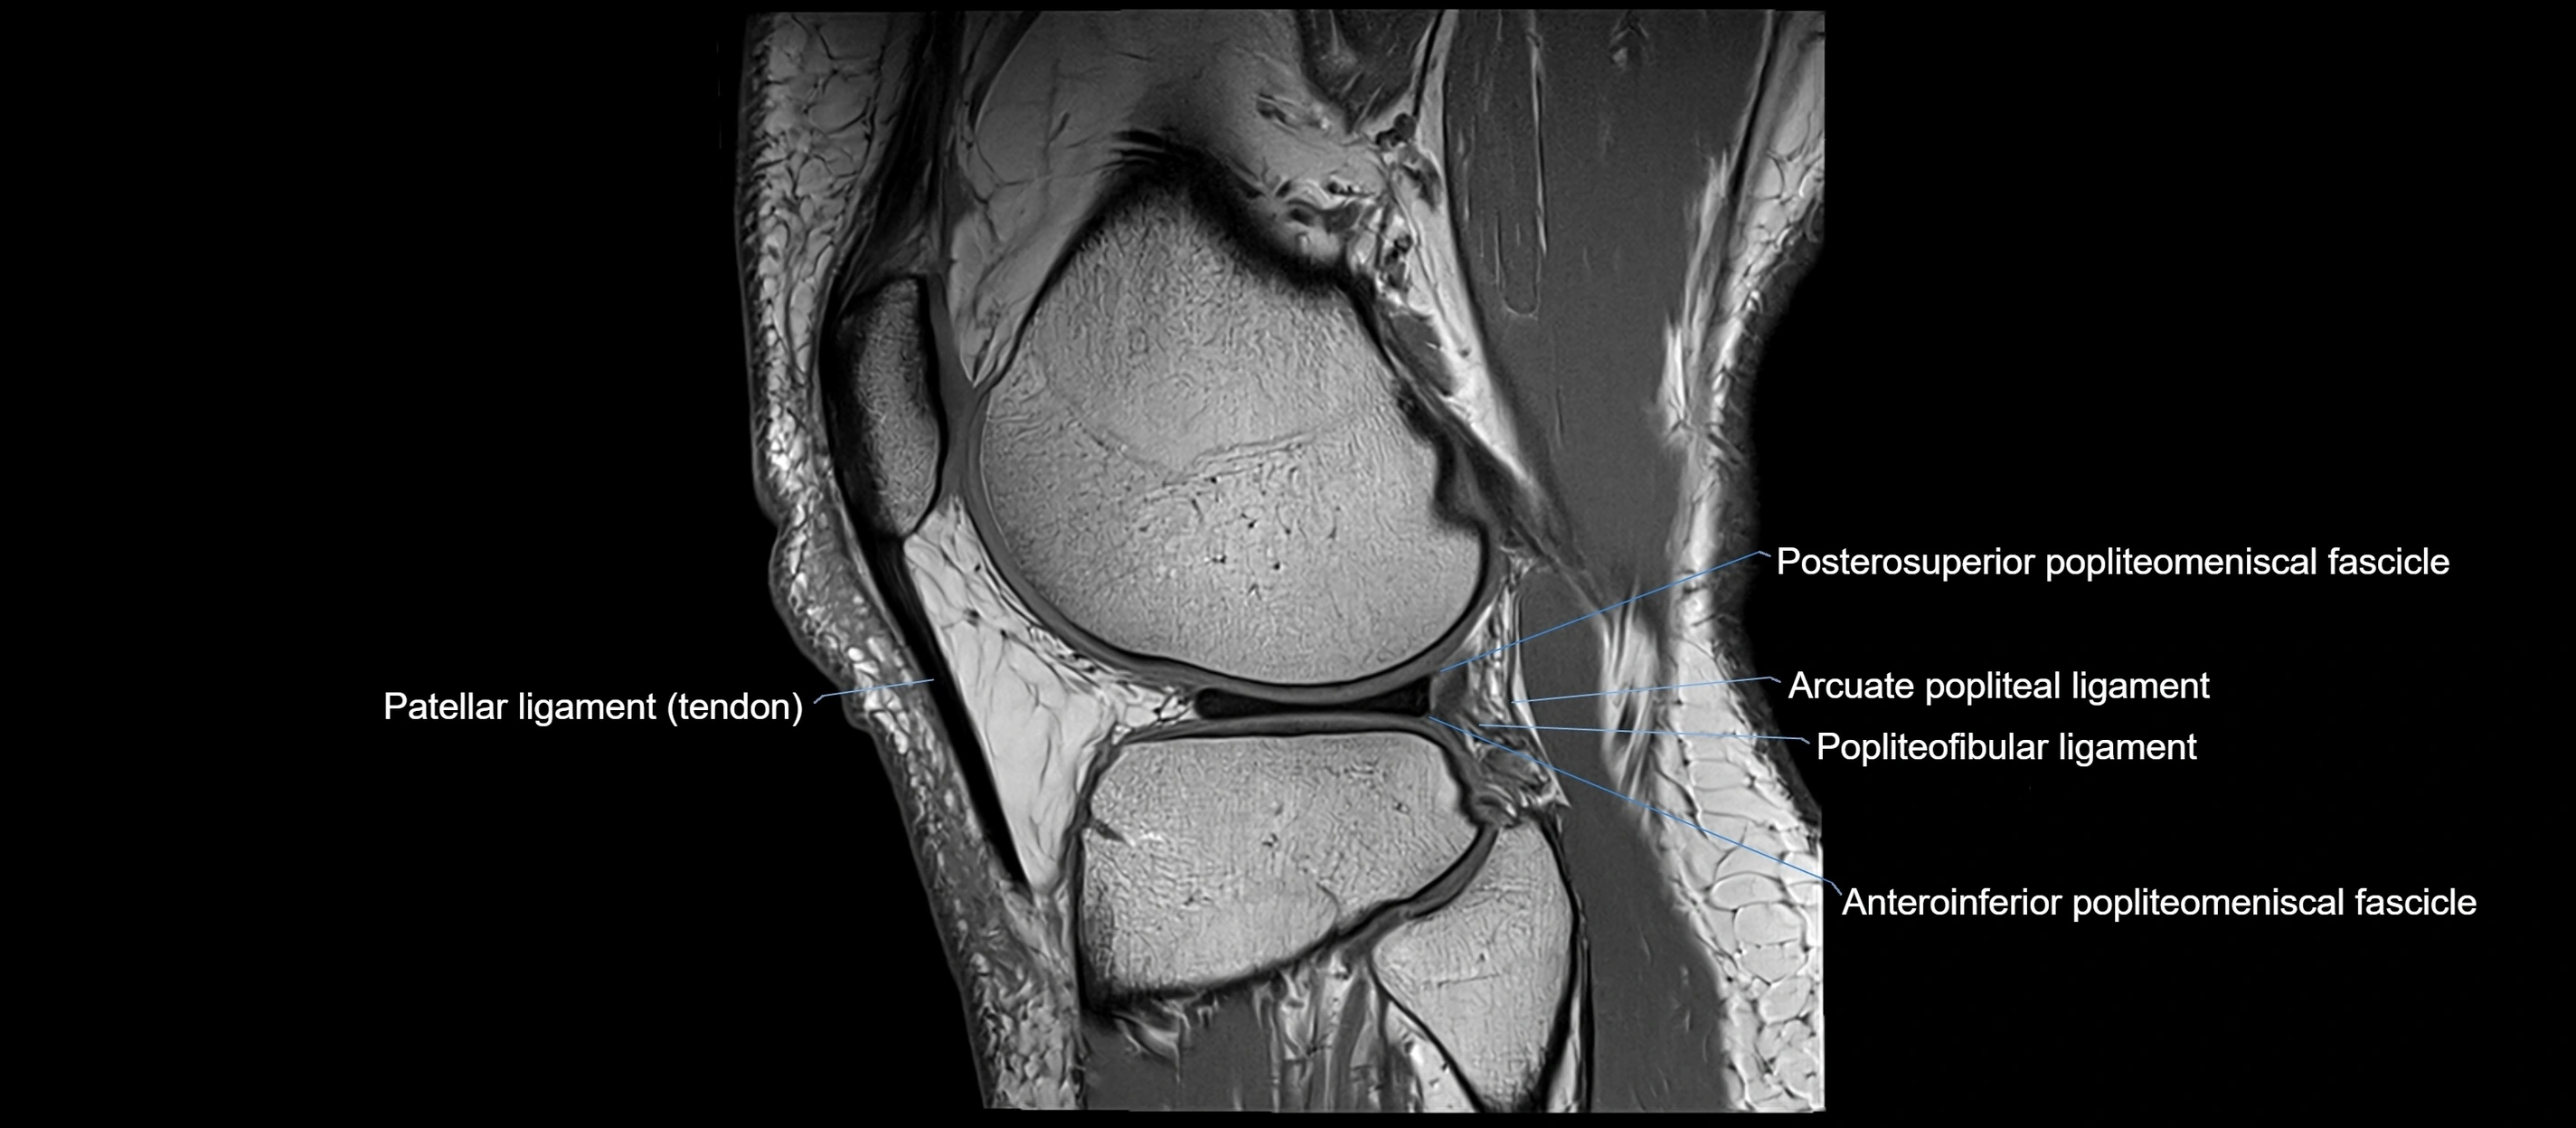

MRI images

image